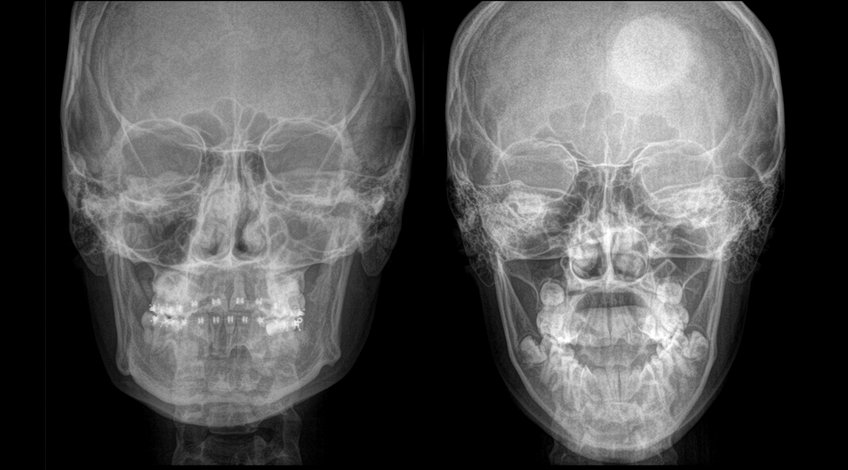

Radiografías, Imagenes de Cara, Malar, Maxilar

Una radiografía de la cara es una serie de imágenes de los huesos de la cara que ayuda a encontrar fracturas, evaluar traumas, infecciones y crecimientos anormales o cambios en la estructura ósea ya sea en la forma o en el tamaño.

Podría ser necesaria una radiografía de cara para encontrar problemas de los senos paranasales de la cara y nariz (pólipos o tumores), revisar los huesos de la cavidad orbitaria, encontrar fracturas en huesos faciales y de la nariz, chequear los senos paranasales antes de una operación, buscar los motivos del dolor de cara, etc.